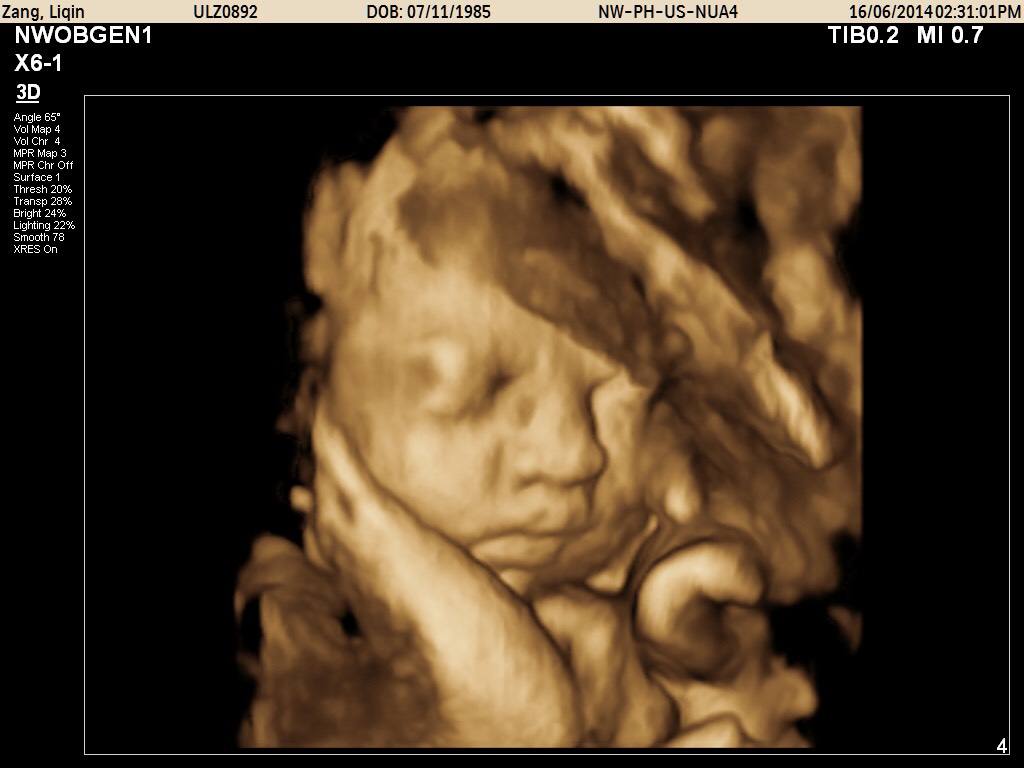

准妈妈一般在12周建档后,医院都会发一份定期产检的单子,写明白什么时间要进行什么样的检查。相信大家最感兴趣的应该就是孕25周后的四维彩超检查。现在的四维彩超技术,不仅能够清晰反应胎儿的样子,在子宫内的活动,医院还会贴心地给父母们拍摄宝宝的第一张彩色照片——四维彩超单。

四维彩超就像我们平时看的3D电影一样,让医生看到子宫内胎儿更为直观、立体的影像。大部分的胎儿四维照显得很丑,或者嘴巴大鼻子大,原因有以下三点。

胎儿在子宫内被羊水包裹,而且将自己的部分排泄废物排到羊水中去,胎儿皮肤上会有一层胎脂,是来保护胎儿肌肤不受羊水伤害的。而胎脂的表面并不光滑,而且并不是均匀分布在皮肤上,若是嘴巴鼻子周围胎脂较多,再加上羊水的放大作用,就会显得胎儿的嘴巴和鼻子特别大。从四维照上可以看出,胎儿头面部位都是凹凸不平的状况,有人戏称好像外星人,那就是胎儿表面的胎脂。